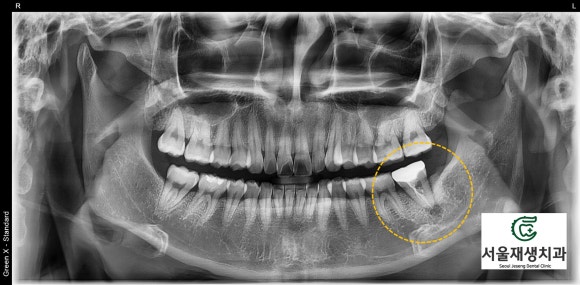

치아 머리에 있던

크라운과 각종 때운 재료들을

모두 제거합니다.

이후, 뿌리에 남아있는

이전 신경치료 재료들,

잔존 감염조직들을 모두

깨끗하게 청소합니다.

마지막으로

소독약제를 도포합니다.

위 엑스레이 사진에서

뿌리 끝까지

약제가 들어간 것을

확인할 수 있습니다.